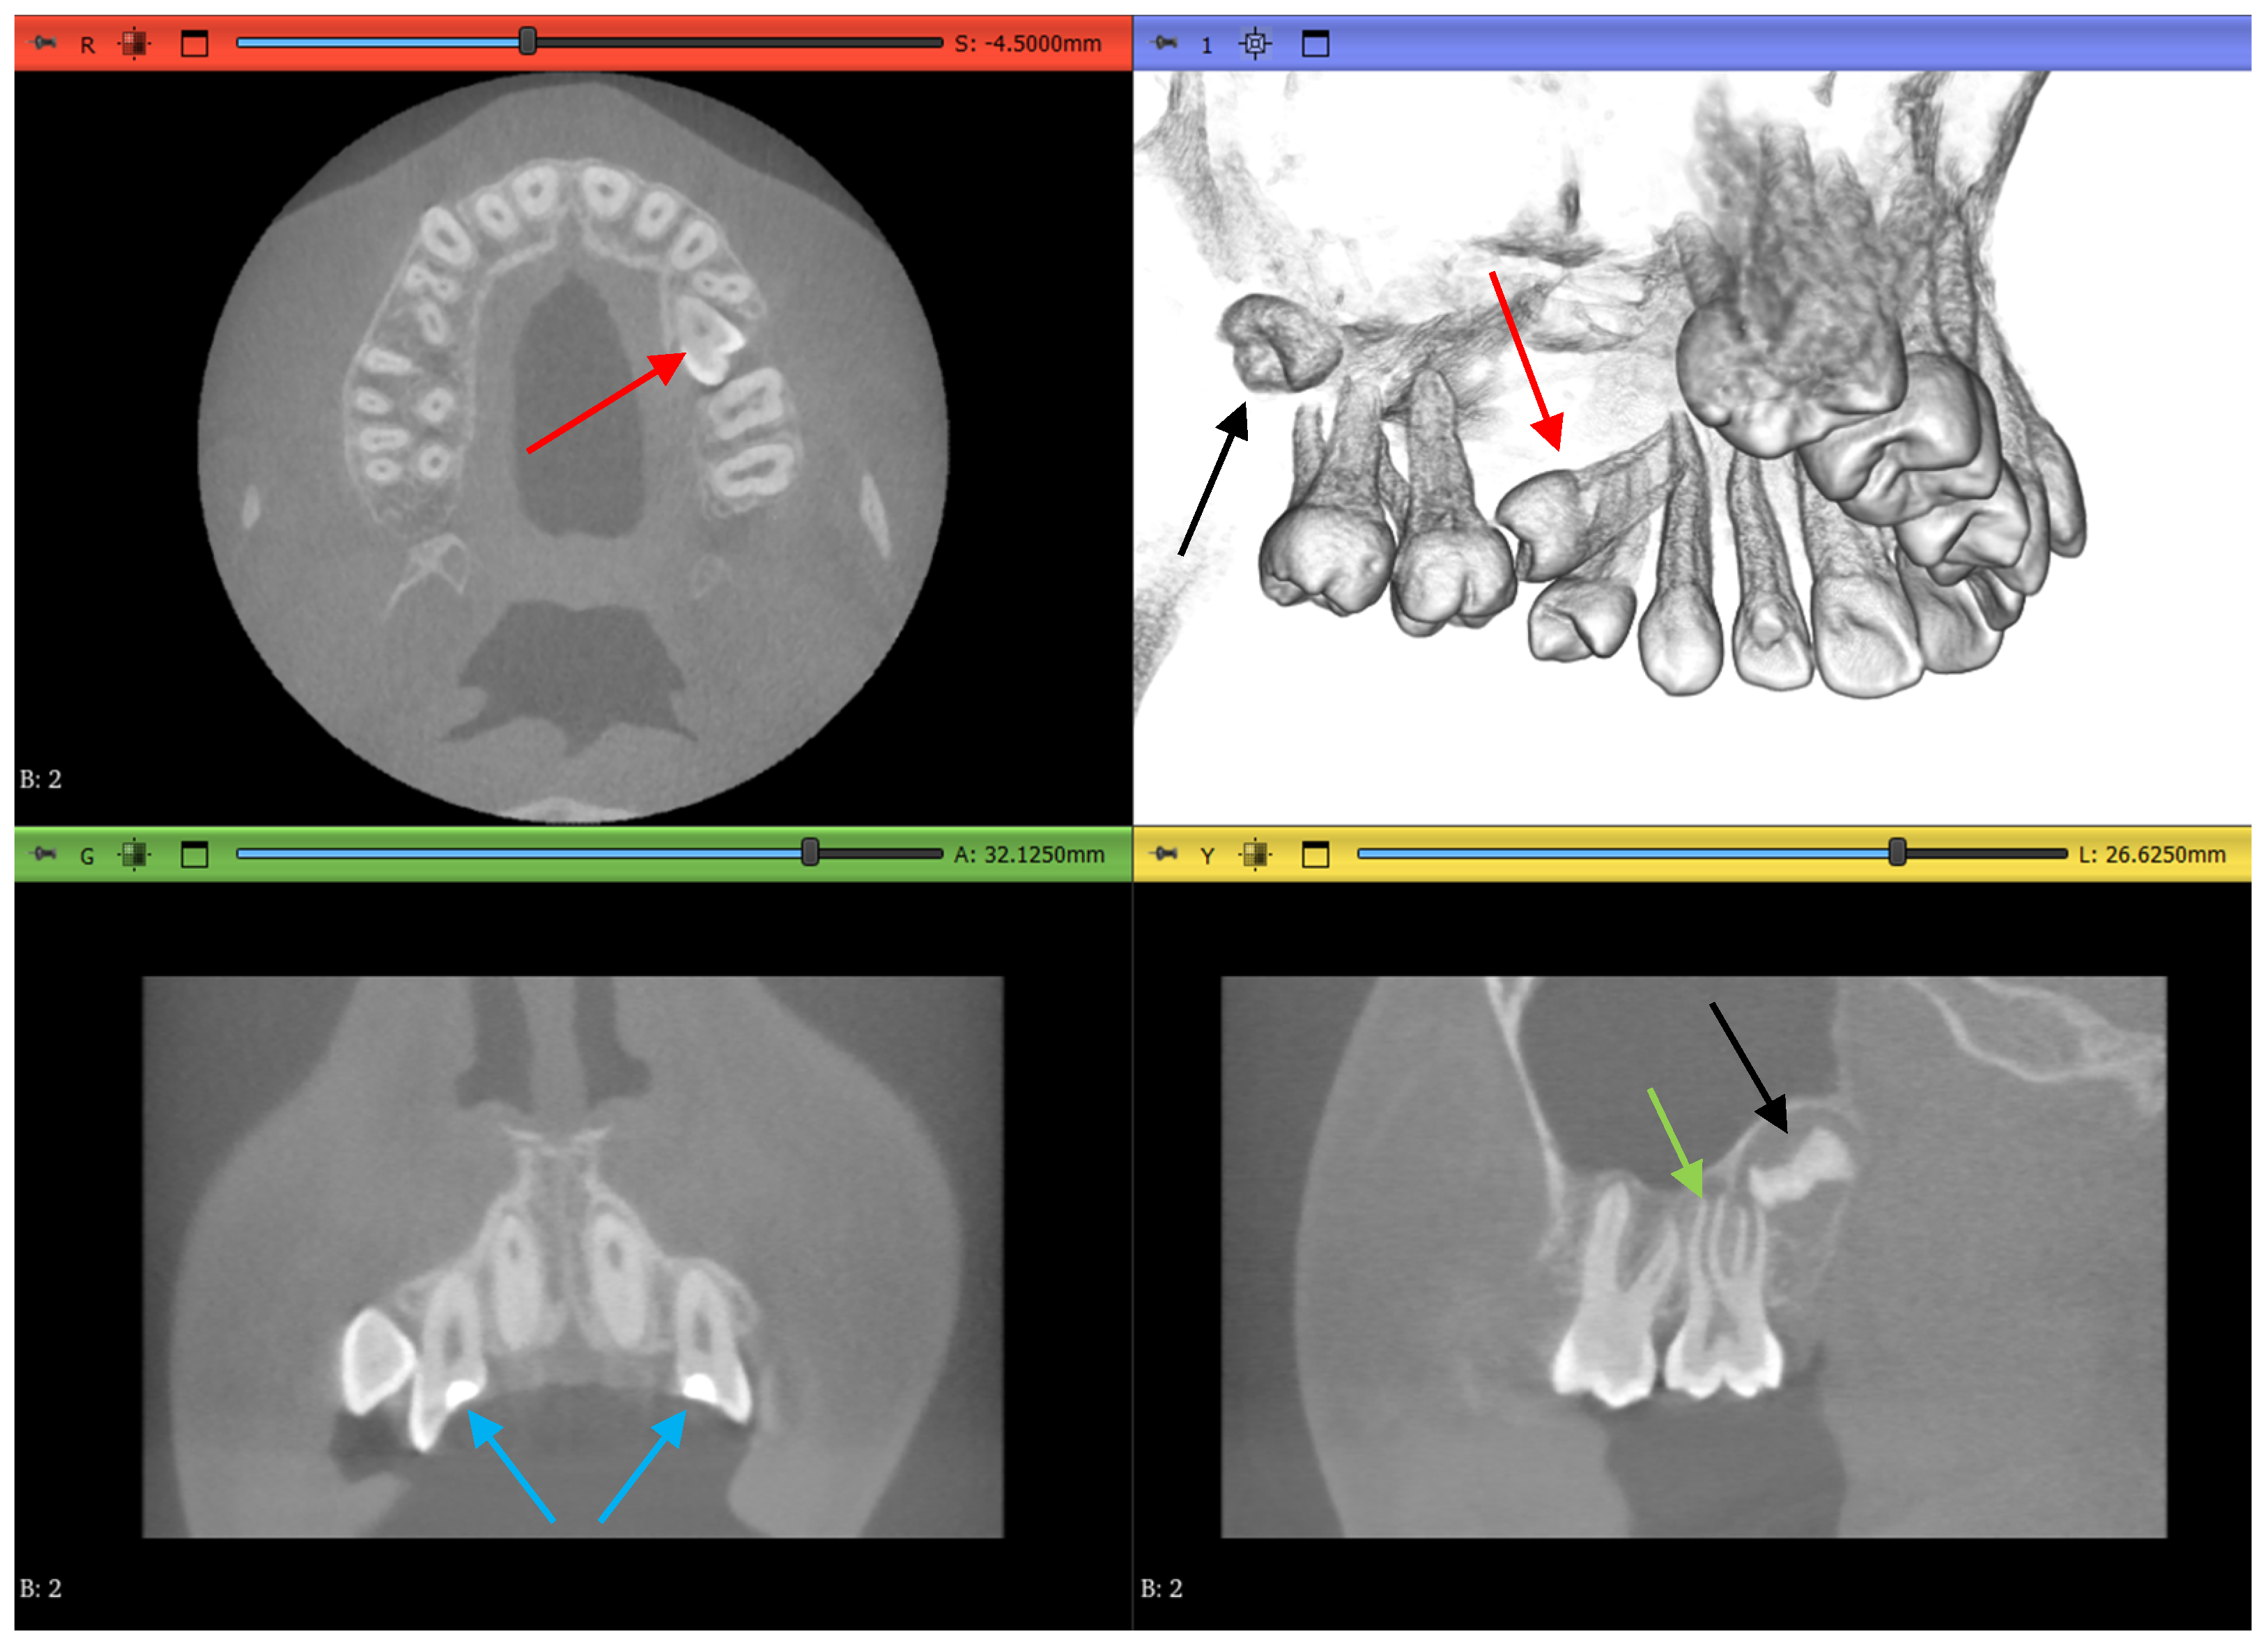

2.1. Datasets

2.3.1. Volume Cropping